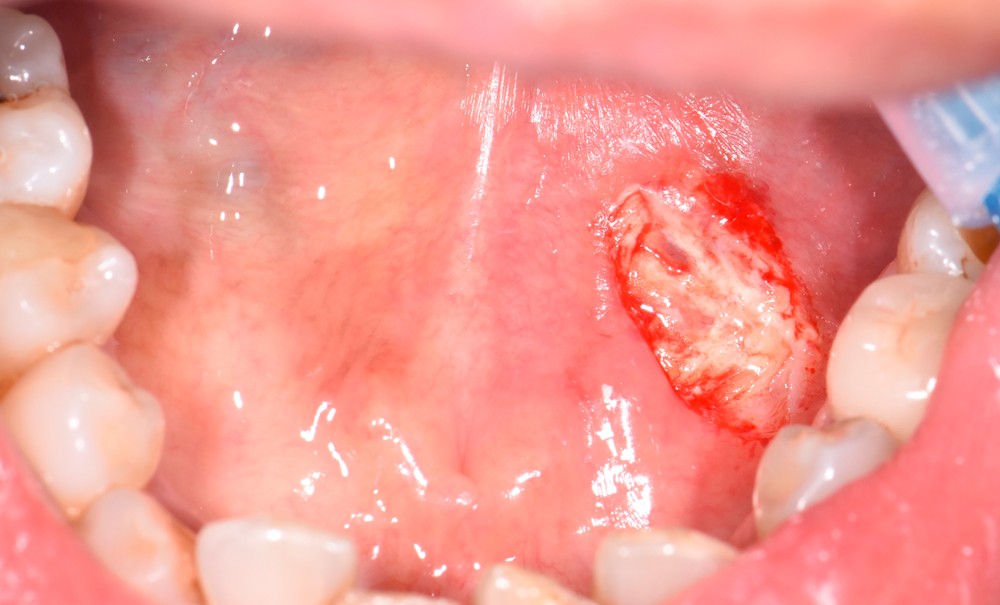

La survenue d’une plaie ou d’une blessure du plancher buccal au cours d’actes odontologiques n’est malheureusement pas si rare. Celles-ci peuvent survenir lors d’actes de chirurgie orale (dérapage de l’instrumentation chirurgicale : élévateur, syndesmotome, fraise à os ou fraise Zekrya, par exemple), ou bien lors de soins prothétiques (instrumentation rotative) intéressant la face linguale du couple prémolo-molaires le plus souvent. La plaie peut être plus ou moins profonde, et son caractère plus ou moins hémorragique en fonction de sa topographie. Un diagnostic et un « bilan lésionnel » doivent être réalisés immédiatement après l’évènement iatrogène, afin d’opter pour une thérapeutique d’urgence et son suivi à distance [1]. Quelle que soit l’étiologie de l’effraction, il convient au praticien de garder son calme, de répondre à son devoir d’information envers le patient, et de le rassurer sur la situation.